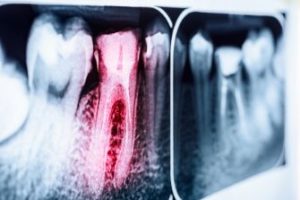

You’ve probably heard the expression, “It will get worse before it gets better.” In some ways, those words could be applied to needing a root canal. After all, it’s bad enough to have a toothache, but then being told you need a root canal can feel like the situation has gone from bad to worse! But even though a root canal sounds terrible, it’s actually much easier than you would expect. Not to mention that a dentist in Long Island City only recommends one so they can save a tooth that would otherwise be lost. But even if root canals are easier and more beneficial than you thought, why do you need one in the first place, when sometimes just a filling or crown is enough? Keep reading to find out!